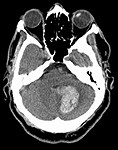

In March 1981, John Hinckley shot President Reagan in an attempt

to assassinate him. At the subsequent trial, no one denied that

Hinckley had fired the shots that had wounded four people; the point

of contention was whether he was sane when he did so.

His lawyers asserted

that he was insane because he suffered from schizophrenia. To buttress

their case, they sought to introduce into evidence a CAT-scan of

Hinckley's brain that revealed it to be atrophied. Because such

atrophy is believed to be present in 30% of schizophrenics but only

2% of others, the attorneys depicted the test result as a powerful

indicator of Hinckley's deranged condition.